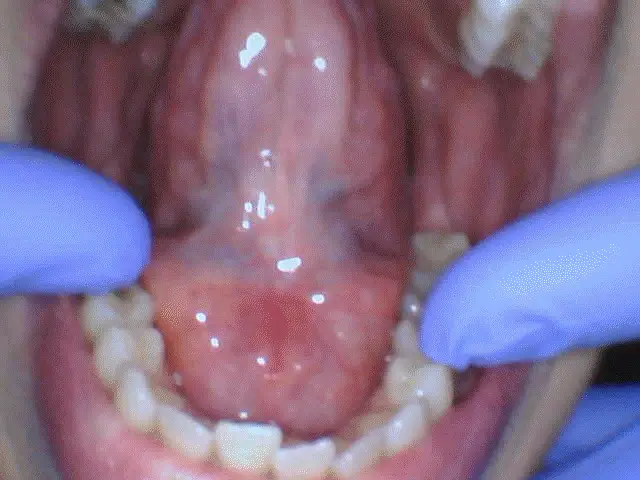

This patient went through a frenectomy, turning what was once a daily struggle into a newfound sense of comfort and ease.

before

after

Frenectomies

After a simple frenectomy, this patient can now enjoy better oral function, improved mobility, and a healthier smile.